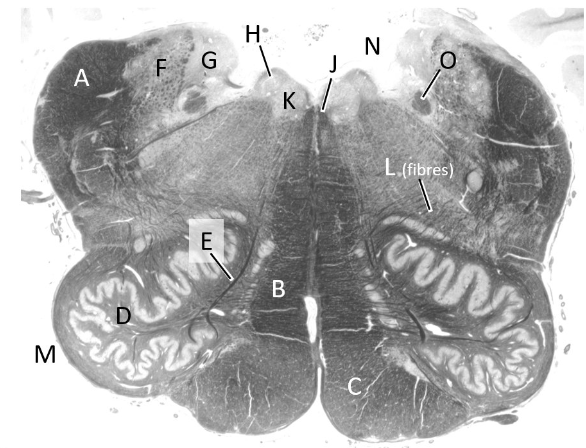

at what level is this?

mid pons

what is a?

cerebellum

what is b?

superior cerebellar peduncle

what is c?

middle cerebellar peduncle

what is d?

trigeminal nerve

what is e?

pyramidal fibres

what is f?

transverse pontine fibres

what is g?

4th ventricle

what is h?

median longitudinal fasciculus (p)

what is j?

medial lemniscus (p)

what is k?

spinothalamic tract (p)